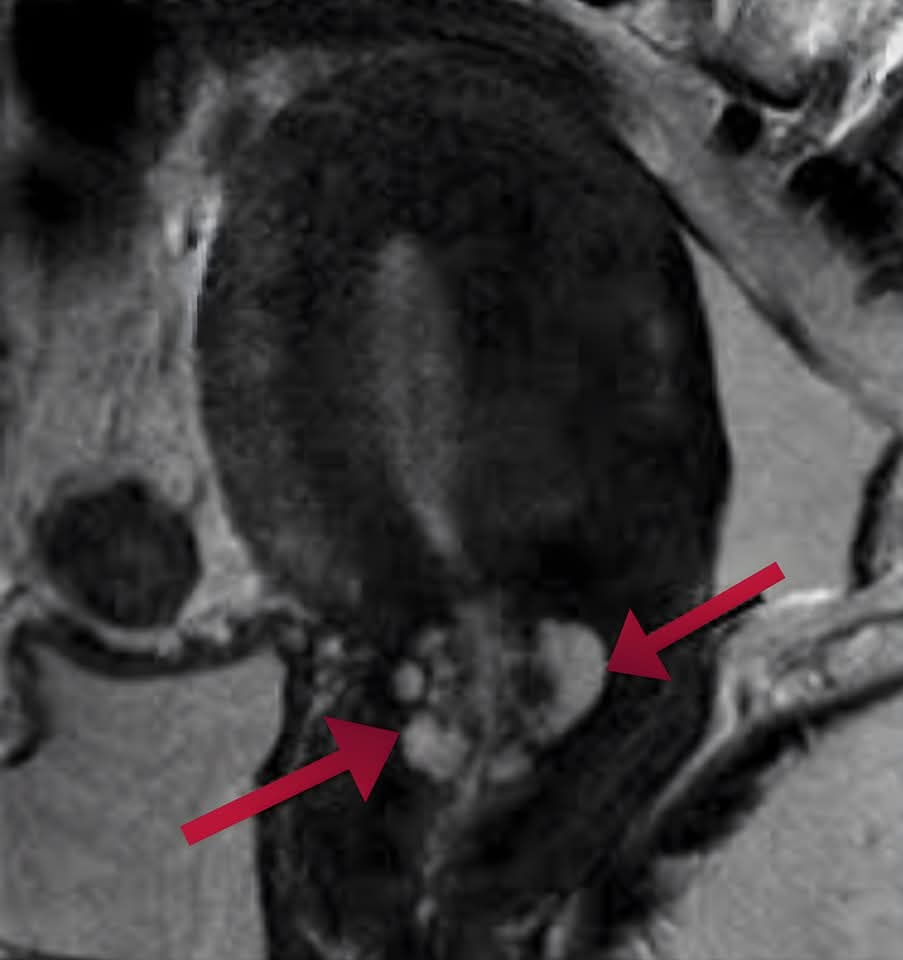

- خلال الفحوصات الدقيقة، تبيَّن وجود *"تجمع كيسي عنقودي"* داخل قنوات عنق الرحم، مما كان يعيق مرور الحيوانات المنوية ويُسبب العقم.

- تم إجراء عملية دقيقة باستخدام *المنظار الجراحي (الهستروسكوب)، حيث أُزيل الانسداد بنجاح **دون أي شقوق جراحية*، وبأقل قدر من المضاعفات.